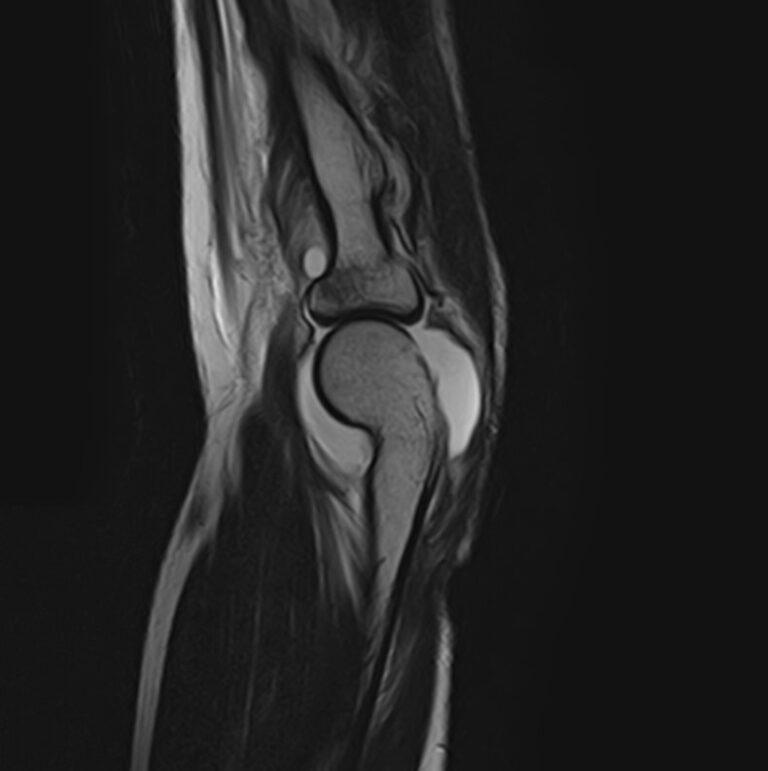

Магнитно-резонансная томография является наиболее информативным методом диагностической визуализации всех структур локтевого сустава, включая костные структуры, связки, сухожилия, прилегающие мягкие ткани. По сравнению с другими методами обследования, такими как УЗИ, рентгенография и компьютерная томография, МРТ позволяет получить наибольшую информацию о патологических процессах в суставе и окружающих тканях, поставить точный диагноз и определить тактику лечения. При этом МР томография не оказывает вредного воздействия на организм, так как технология процесса не предусматривает использование рентгеновского излучения.

В клинике «Доступная медицина» проводится МРТ локтевого сустава на современном томографе закрытого типа TOSHIBA VANTAGE TITAN 1,5 Тесла. Благодаря высокой мощности магнитного поля устройство при сканировании выявляет даже минимальные очаги поражения сустава и на основе полученных данных проводит построение 3D-модели. Кроме того, для увеличения информативности МРТ в некоторых случаях применяется введение контрастного вещества, содержащего в своем составе металл гадолиний.